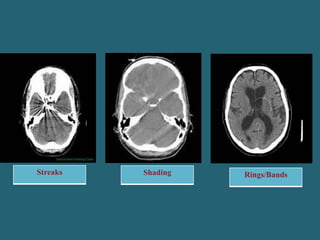

On the basis of Appearance:

Appearance Cause

Streaks - Improper sampling data, partial volume average, Pt motion, Beam

hardening, Noise, spiral/ helical, Mechanical failure

Shading - Partial volume averaging , Beam hardening, Spiral/ Helical,

Scatter radiation, Off focal radiation , Improper projection

Rings/Bands - Bad detector channel

Streaks Shading Rings/Bands